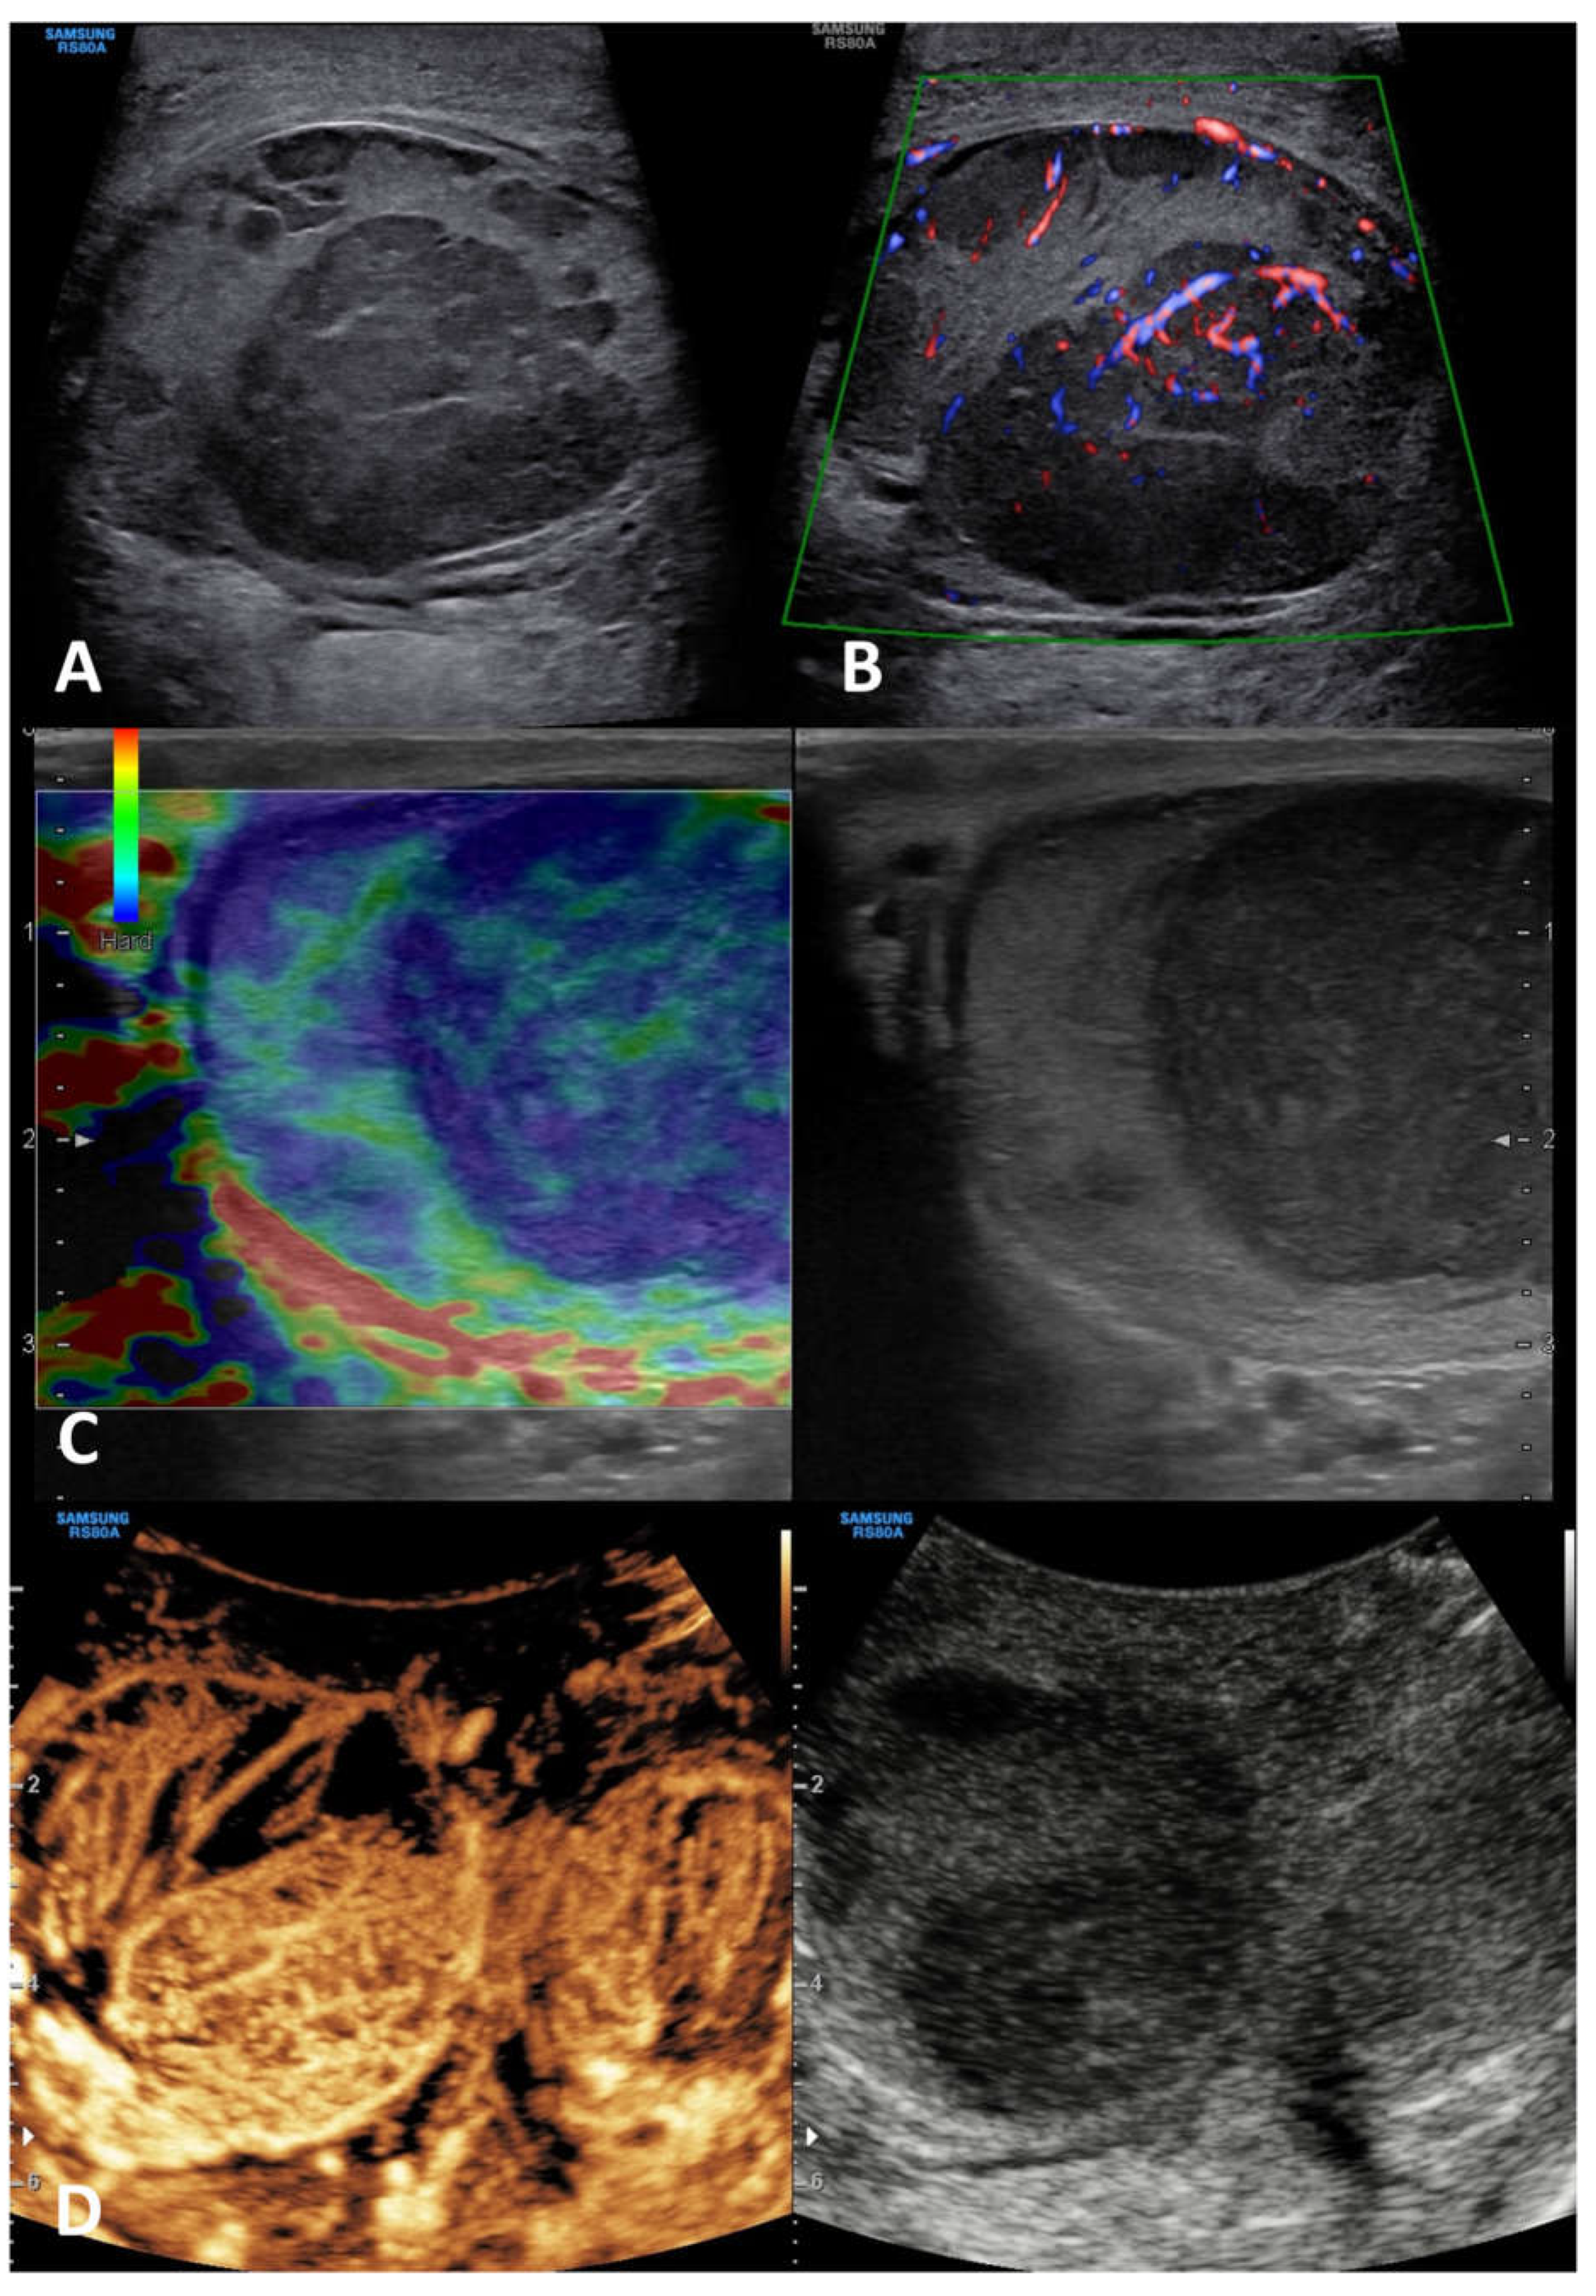

6.3.1. Leydig cell tumor (LCT)

| Neoplastic intratesticular lesions | ||||||

| Clinical presentation | Serum tumor markers | GSUS | CDUS | CEUS | SE | |

| Leydig cell tumor | Generally asymptomatic; it can produce androgens | Negative | Hypoechoic, homogeneous well demarcated lesion (possible hyperechoic halo) |

Hypervascularized | Homogeneously hyperenhanced (rapid wash-in, delayed wash-out) |

Hard lesions with low/absent elastic strain |

6.3.2. Sertoli cell tumor (SCT)

| Sertoli cell tumor | Asymptomatic; they can be a part of multiple neoplasia syndromes, such as Carney Complex and Peutz-Jegers | Negative | Hypo- or hyper-echoic lesion, with possible calcifications | Hypervascularized | Homogeneously hyperenhanced |